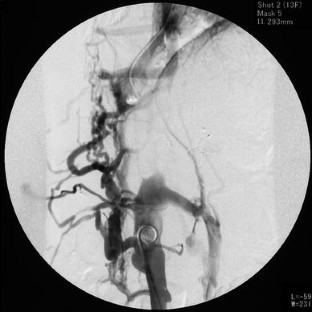

Fig. 3